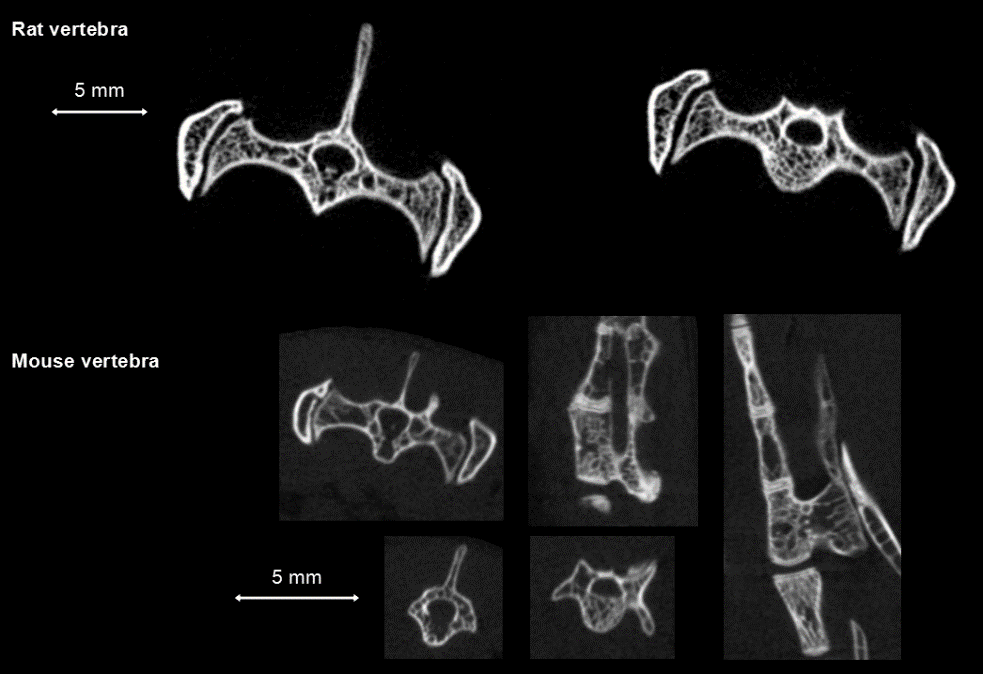

鼠的脊椎骨活體測量:高清晰度環(huán)形獲取,獲取時間:4min,F(xiàn)DK重建,50和20μm voxel size。

脊椎骨測量.png